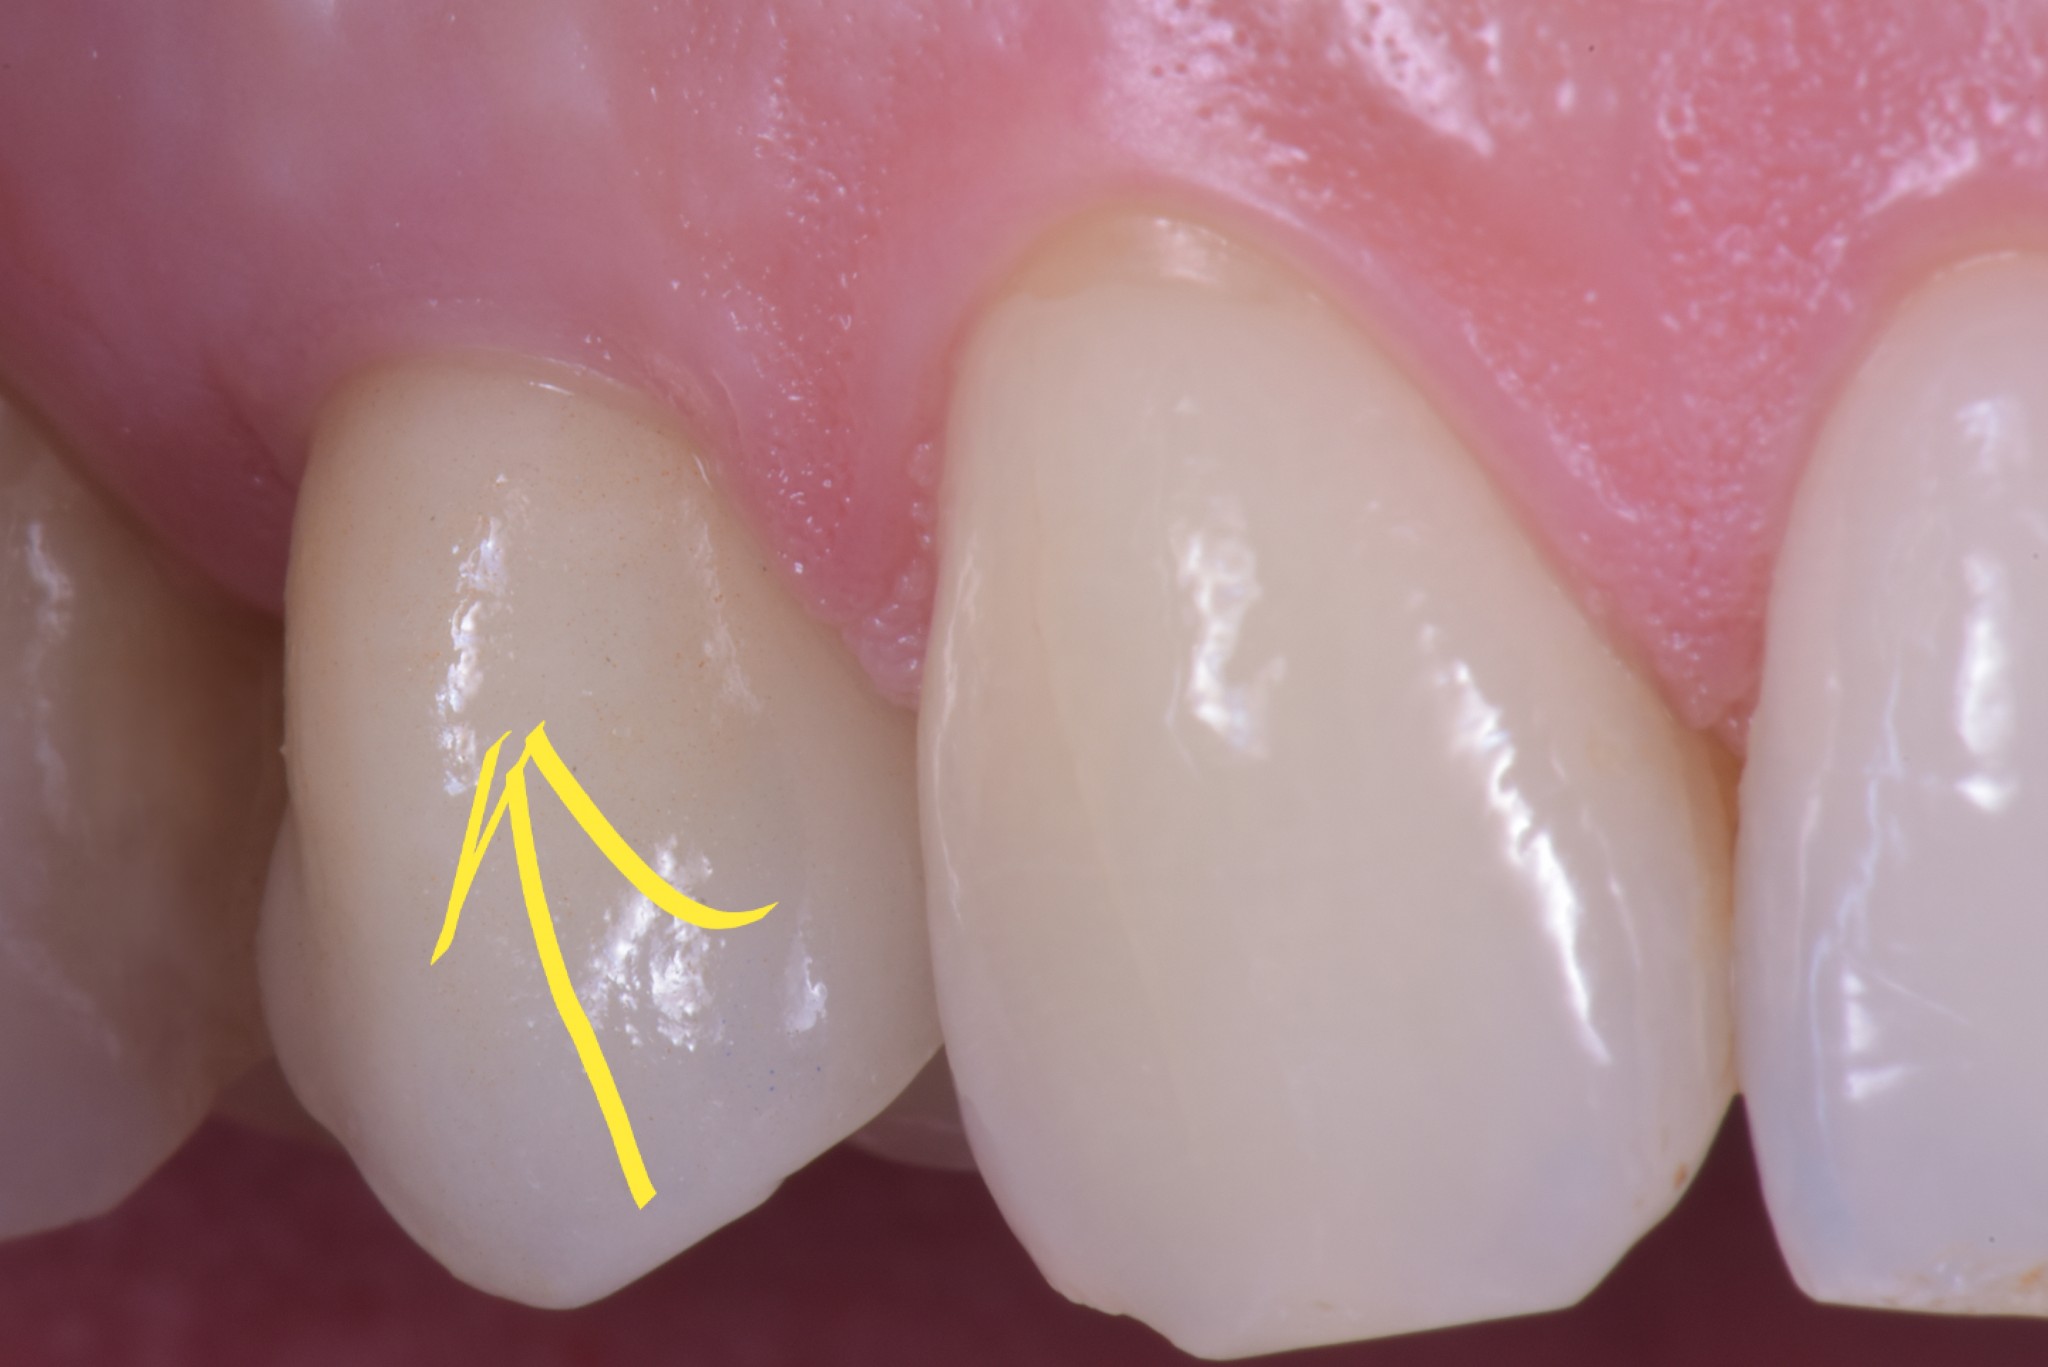

Un dente su impianto oggi ha la possibilità di avere questo aspetto

gestione dei tessuti molli - esempio premolare